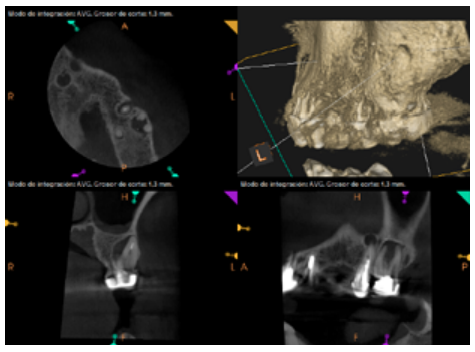

To confirm the endodontic origin and the size of the lesions, tomographic examinations were performed with a slice thickness of 75 microns using CBCT CS8100 (Carestream Dental™), in which radiolucent periapical lesions were observed at the level of 12, 11, 21 (with bicortical involvement), 25 and vestibular roots at 26 (Figures 4 to 8).

Meanwhile, the vestibular roots of 26 showed clearly deficient root canal treatment, being underextended by several millimetres, as well as an omitted mesiopalatine canal (MP). Therefore, the need to repair the root canal treatment was proposed to the patient before performing microsurgery on tooth 25 (Figure 9).

Six months later, the patient went for a check-up without any symptoms, both anteriorly and posteriorly. Periapical radiographs showed a decrease in the size of the pre-existing radiolucent periapical lesions (Figures 10 and 11). Given that the lesion on 25 remained to be treated, a control CBCT was performed where improvement at the level of 26 was verified (Figure 12), so microsurgery on 25 was scheduled.

After the microsurgery was performed on 25, the patient had no symptoms and the control tomographies at 12 months (in 25) and at 18 months in the remaining teeth showed regeneration of pre-existing radiolucent periapical lesions on all treated teeth (Figures 13 to 16).